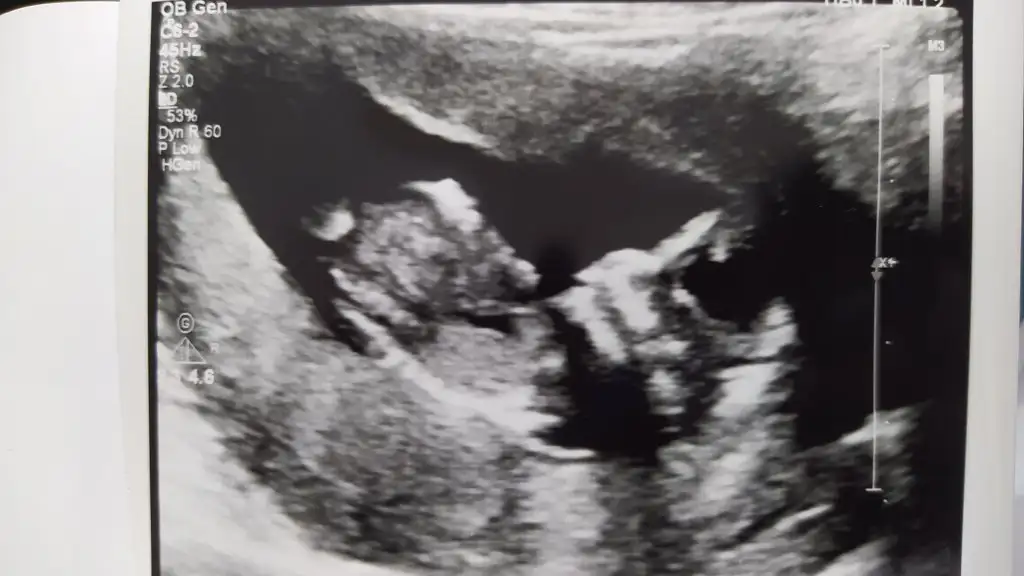

Banada yorum yaparmisinizUltrason resimleriniz varmı?? Ordan tahmin edebilirim

Ultrason resimleriniz varmı?? Ordan tahmin edebilirim